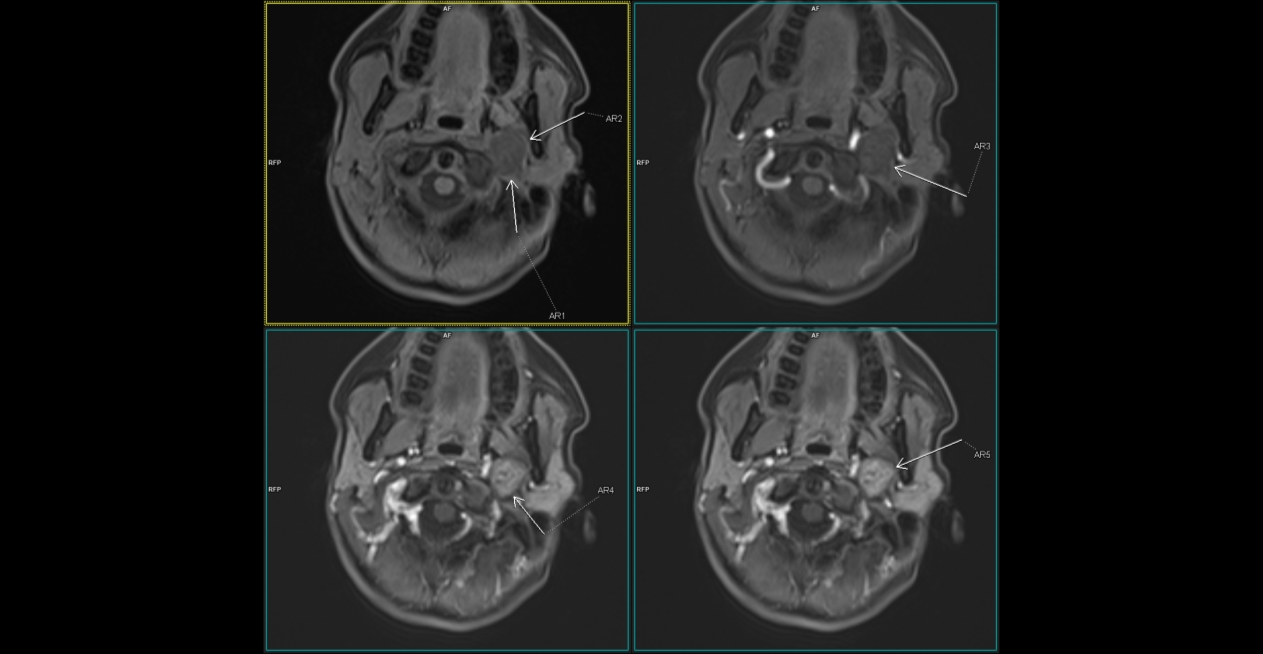

Figura 1: patru imagini în paralel la nivelul regiunii cervicale pentru analiza comportamentului leziunii la administrare dinamică a substanței de contrast la examinarea IRM

Discuţie caz nr 129: pacientul este trimis la examinare IRM cu suspiciune ecografică de adenopatie latero-cervicală. Se evidențiază o leziune rotund-ovalară în hipersemnal T1 și T2 comparativ cu musculatura scheletică, net delimitată, fără restricție de difuzie a apei, cu priză progresivă de contrast, pe traseul nervului vag. Principalele diagnostice diferentiale: glomusul carotic (priza de contrast precoce de tip flash arterial, este situată în vecinătatea bifurcației carotidiene), adnopatie latero-cervicala, chiste de arc branhial.